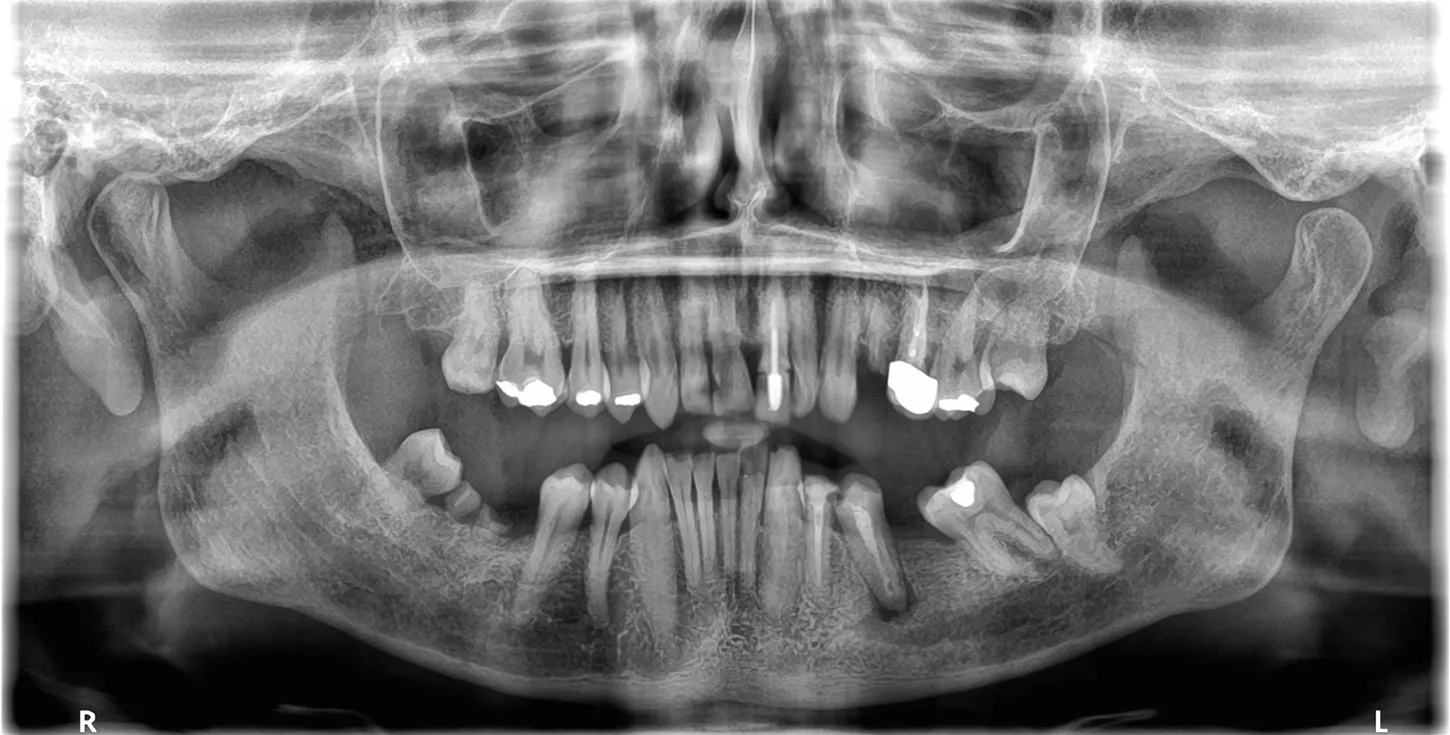

1. Panoramic view showing severe bone loss around tooth 15, confirming hopeless prognosis.

1

9. Panoramic radiograph taken on the day of implant placement.

9